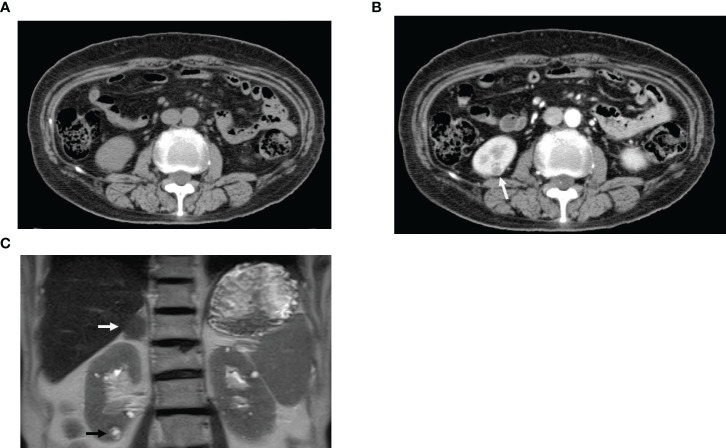

A kidney biopsy was performed in a 64-year-old woman with type 2 diabetes mellitus and less than 1 g of proteinuria who rapidly progressed to end-stage renal failure after approximately 2 years of treatment with two dipeptidyl peptidase 4 (DPP-4) inhibitors for type 2 diabetes mellitus. The biopsy revealed not only a coincidental diagnosis of renal cell carcinoma, which was not evident on pre-biopsy computed tomography, but also severe thrombotic microangiopathy (TMA)-like glomerular endothelial cell damage in the noncancerous areas. These results suggest that DPP4 inhibitors may have been involved in two kidney diseases.